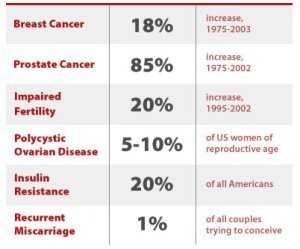

Growing Evidence of Links Between BPA and Autism, Cancer, Diabetes, Myriad Health Problems

I found that The Sleuth Journal is reliable. Below is an informative, well-researched article with this and other great infographics, a video, and more.

image from “Ban BPA From Your Life: 6 Small Steps That Will Help You Live Toxin-Free” http://www.thesleuthjournal.com/ban-bpa-from-your-life-6-small-steps-that-will-help-you-live-toxin-free/, “Page by T SJ – Almost 5 decades later, scientists began seeing disturbing correlations between exposure to BPA and obesity, impaired brain development, various types of cancer, [and other health problems.]“

BPA is Even Worse for Babies and Girls/Adult Females

Common Folk is another reliable source for information. Many European countries are so far ahead of the USA in understanding and refusing to tolerate chemical toxicity and GMO (Genetically Modified Organisms) in their food, agriculture and beverages. We should all learn from and imitate what they’re doing. Avoiding/reducing endocrine disruptors, especially because of their adverse effects on babies and females, is just one of the many areas the EU folks are smarter about than the USA.